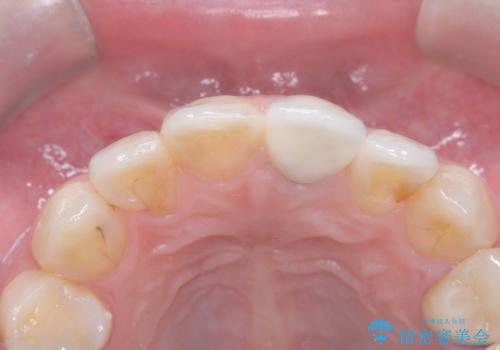

オールセラミッククラウンで治療を行い見た目の改善を行いました。

右上1もCRが入っており治療を勧めましたが、希望されず左上1のみ行いました。

色味は左上2に合わせたいとのご希望だったので、左上2に合わせています。